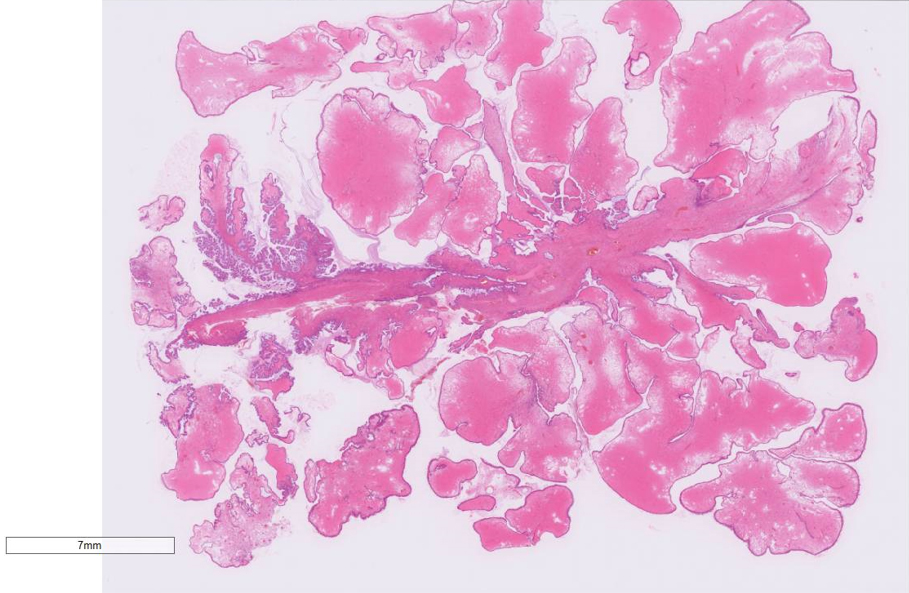

• HE ルーペ像